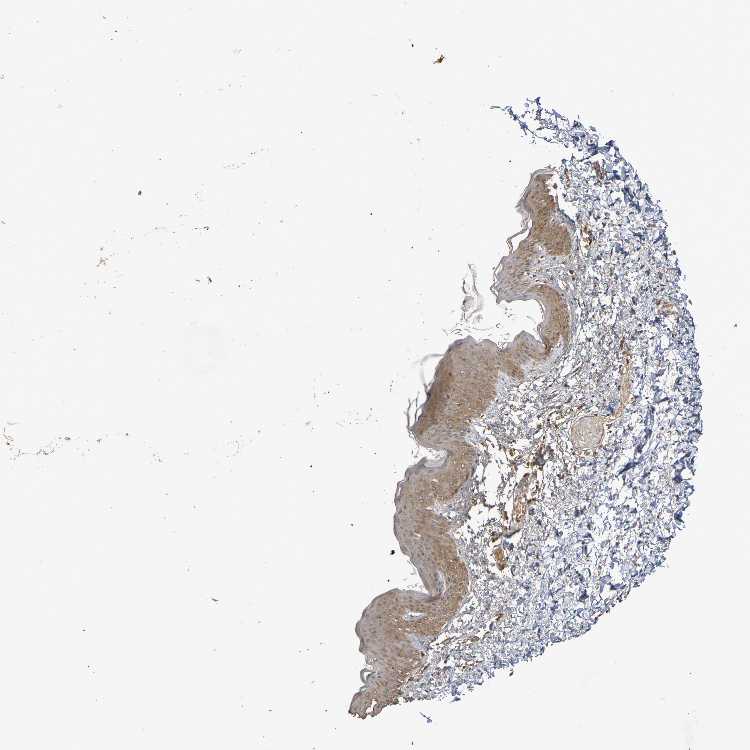

TISSUE PRIMARY DATA SKIN Show tissue menu

SKIN 1 - Antibody stainingi

Antibody staining in the annotated cell types in the current human tissue is reported as not detected, low, medium, or high, based on conventional immunohistochemistry profiling in selected tissues. This score is based on the combination of the staining intensity and fraction of stained cells.

Each image is clickable and will lead to virtual microscopy that enables deeper exploration of all samples and also displays staining intensity scores, fraction scores and subcellular localization as well as patient and tissue information for each sample.

Antibody HPA001907Antibody HPA002735Antibody CAB010451Antibody CAB080271

Langerhans MediumMediumMediumHigh

Fibroblasts MediumMediumLowNot detected

Keratinocytes HighMediumMediumHigh

Melanocytes MediumMediumMediumHigh